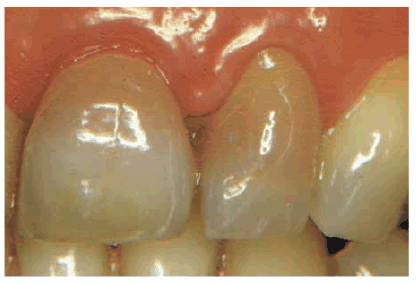

severe inflammatory reaction is greater. If a pink spot in the cavity or a

blush on the tooth appears (Figures 19-33A, and 19-33B) during or after preparation, it is

obvious that the 2-mm remaining dentin barrier has been violated. The

probability of complete inflammatory reversibility and healing of a noticeably

hemorrhagic pulp is minimal. Considering that additional procedures are

required to finish the crown, elective endodontics should be instituted before

continuing. If, at any time, a patient elects to forego endodontic therapy

Figure 19-33A: Pink crown preparation 1 week following instrumentation.

Figure 19-33B: Hemorrhagic pulp with extravasation of blood. (Photograph courtesy of Dr. Harold R. Stanley.)